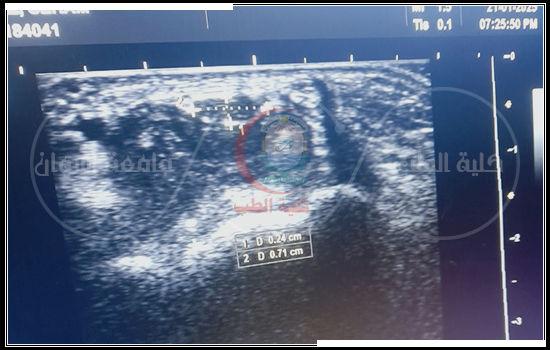

- سونار وحقن لمفصل الكتف الأيمن لمريضه تعانى من متلازمه إصطدام أوتار الكتف وإلتهابات بالأوتار وخشونة بمفصل الاخرمى الترقوى.

- سونار وحقن لمفصل الكتف الأيمن لمريضه تيبس كتفى.

- سونار لمفصل الكتف الأيسر لمريض تيبس كتفى وتم حقن المفصل وعمل حصار عصبى للعصب الفوق كتفى.

- سونار وحقن لمفصل الكتف الأيسر لمريضه تعانى من إلتهابات بأوتار الكتف.

- سونار وحقن لمريضة تعانى من إلتهابات بالوتر الفوق شوكى لمفصل الكتف الأيمن.